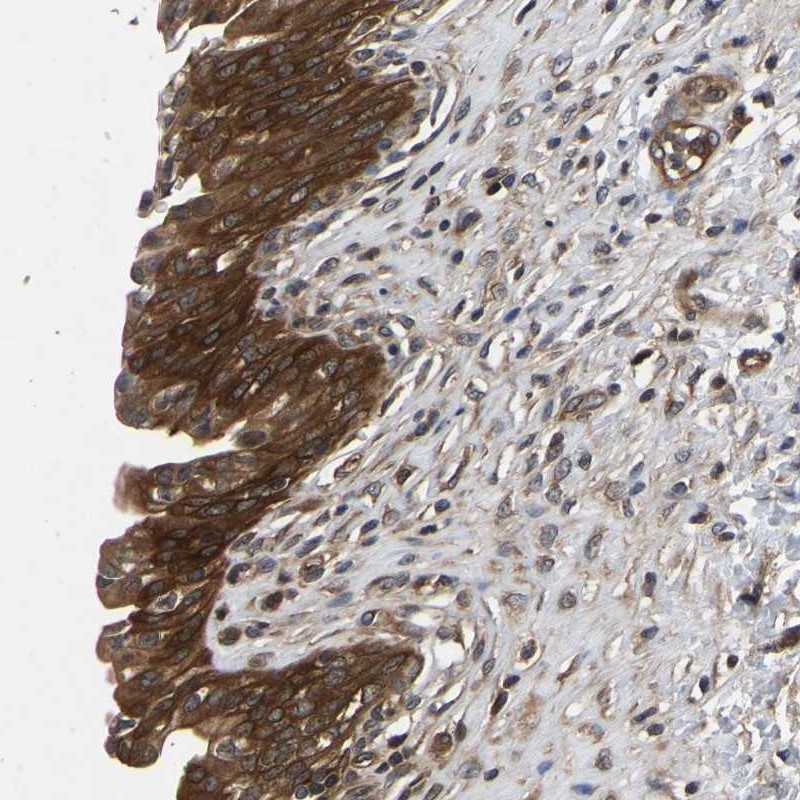

Immunohistochemical staining of human urinary bladder shows strong cytoplasmic positivity in urothelial cells.